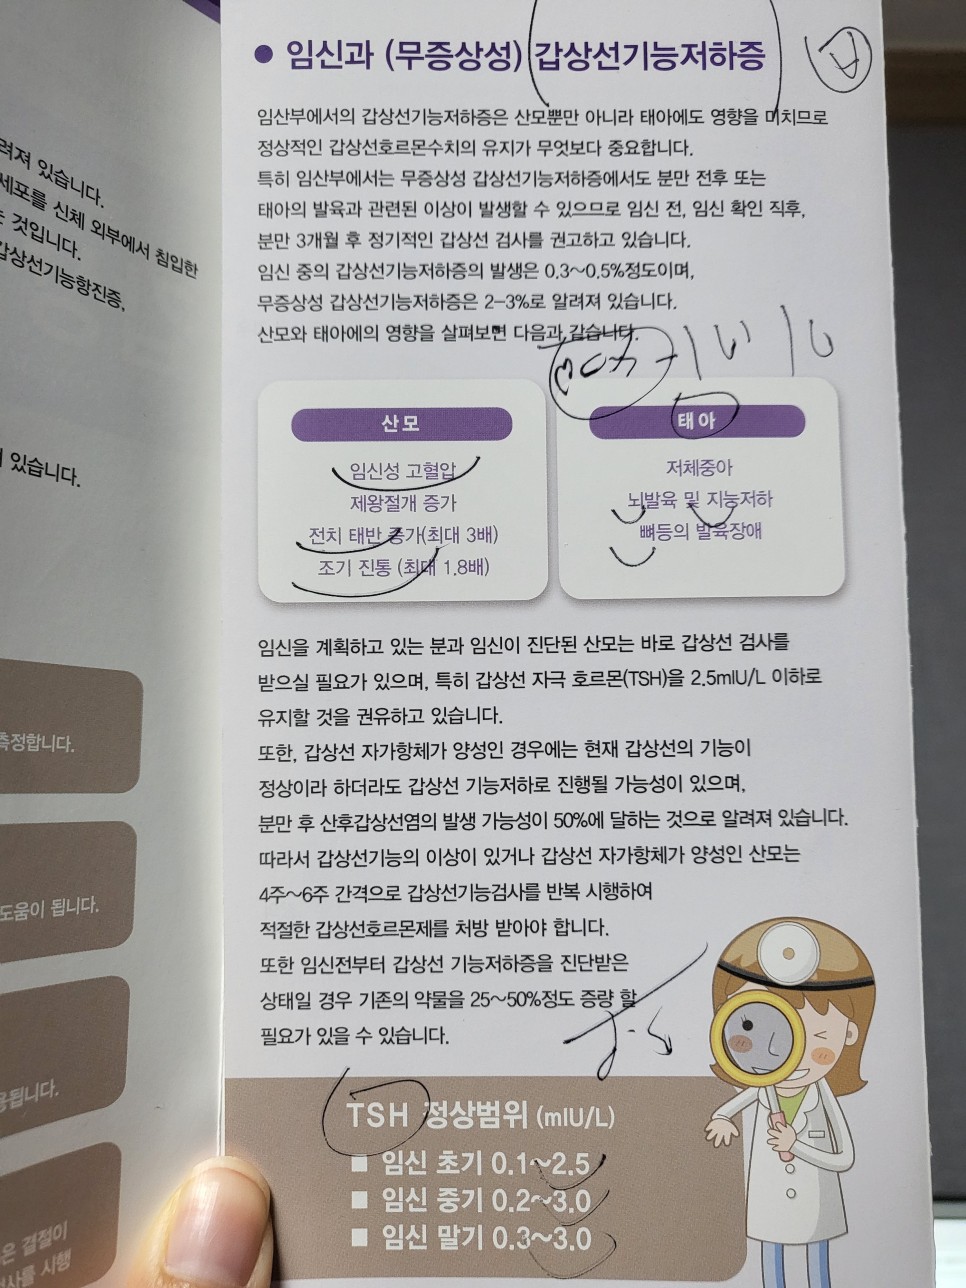

검색과 이전에 회사에 근무했을 때의 기억을 약간 되살려 보면 갑상샘 자극 호르몬이 높은 것은 갑상샘 기능 저하증이라고 할 수 있었다.

어? 왜? 호르몬 수치가 높으면 항진증 아니야?라고 생각할 수 있지만 갑상샘 호르몬과 갑상샘 자극 호르몬은 다르다.

갑상선 자극 호르몬이 많이 분비되는 이유는 갑상선에서 나오는 갑상선 호르몬이 부족하기 때문에 ‘갑상선 기능 저하증’이다.

임신초기의 정상범위보다 2배이상 나왔네…ㅠㅠ이건 뭐야ㅠㅠ

이것이 임신부에게 일시적으로 일어나는 현상인지, 아니면 갑상샘 자체에 문제가 생겨 수치가 올라갔는지 초음파 검사를 해봐야 한다고 말했다.

다행히 초음파 결과상 갑상샘의 모양에 이상이 있는 것은 아니었다.임신했다면 내 갑상샘호르몬이 태아에게 가서 갑상샘호르몬이 부족한 것 같은데.. 갑상샘호르몬은 태아발육에 지대한 영향을 미쳐 갑상샘호르몬약을 복용하는 것이 산모에게 부작용을 일으키지도 않는다.오히려 약을 먹지 않는 것이 태아에게는 매우 좋지 않다는 것.갑상선 수치를 걱정하는 임산부는 걱정하지 말고 약을 복용해 주시기 바랍니다!현재 14 주째인 저 역시 하루에 한 알을 꼬박꼬박 먹고 있습니다.